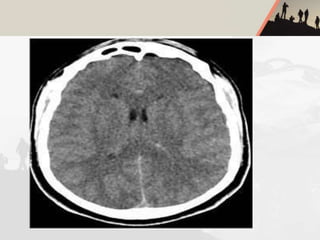

HIGH ALTITUDE CEREBRAL

OEDEMA(HACO)